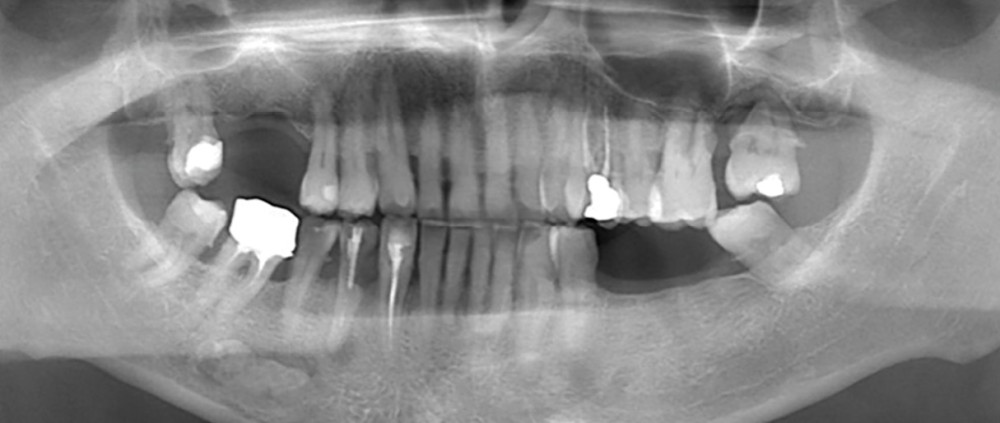

- Quelle anomalie radiologique observez-vous sur cette radiographie panoramique ?

- Comment la nommeriez-vous ?

- Quels diagnostics différentiels pourraient être évoqués ?

- Quels examens complémentaires et/ou quelle conduite à tenir recommanderiez-vous ?

Observations : Outre les constatations habituelles (dents dévitalisées, point sur les 3e molaires, etc.) et outre la calcification des ligaments stylo-hyoïdiens droit et gauche, on observe en regard de la dent 36, au niveau sous-apical, une image radio-opaque arrondie, bien limitée, indépendante des racines. La dent 36 apparaît vitale, indemne de lésion carieuse ou de remaniement péri-apical.

Interprétation : L’aspect évoque en première intention une ostéosclérose idiopathique. Une lithiase salivaire (ou sialolithiase, affection définie par la formation de calculs ou sialolithes) pourrait également être discutée, de même qu’un ostéome périphérique (tumeur bénigne constituée d’os dense normal) en projection sur ce cliché. Toutefois, la morphologie et la localisation sont en faveur d’une forme idiopathique.

Conduite à tenir : Un suivi radiologique régulier est à préconiser au moyen d’une radiographie panoramique tous les deux ans. Aucun examen complémentaire n’est nécessaire en l’absence d’évolution atypique ou de caractéristiques radiographiques suspectes. Si nécessaire, pour asseoir définitivement le diagnostic, un CBCT peut être réalisé (petit champ : champ 4×4, dose 188mGy.cm², voxel 125 µ).